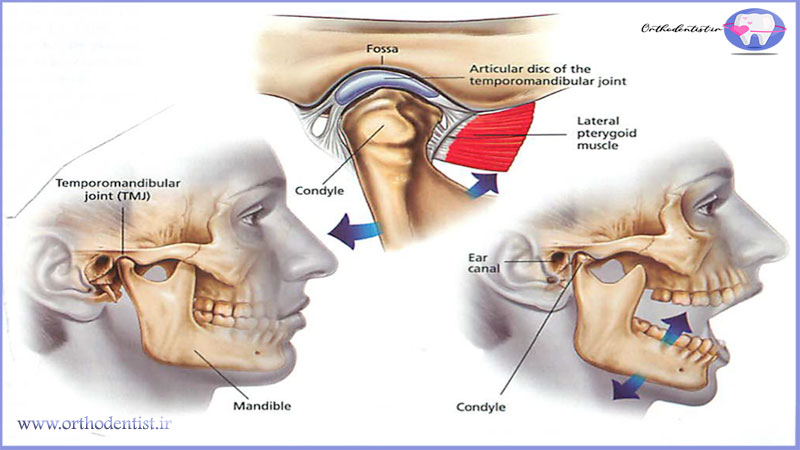

اختلال مفصل فکی گیجگاهی یا TMJ، مفصل فکی گیجگاهی را درگیر میکند این مفصل، استخوان فک را به جمجمه متصل میکند و مانند مفصل لغزاننده عمل مینماید.

اگر مکانیسم مفصل لغزاننده که فک بالا و پایین را به یکدیگر متصل میکند، عمل نکند باعث بروز درد در مفصل فکی و عضلاتی میشود که حرکات فک را کنترل میکنند.

منظور از اختلال مفصل فکی گیجگاهی (TMD)، مشکلاتی است که بر مفصل فکی گیجگاهی، عضلات فک و اعصاب صورت تاثیر میگذارد.